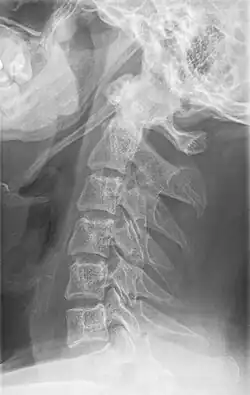

Anteroposterior and lateral radiographs of cervical spine showing ossification of the stylohyoid ligament on both sides

Imaging is important and is diagnostic. Visualizing the styloid process on a CT scan with 3D reconstruction is the suggested imaging technique.[13] The enlarged styloid may be visible on an orthopantogram or a lateral soft tissue X ray of the neck.